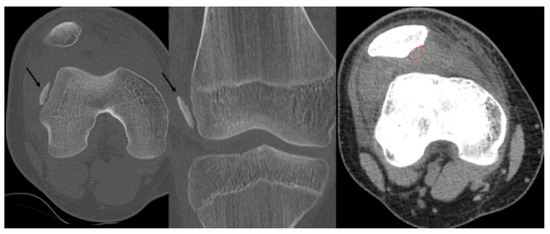

Second patient: A fifteen-year-old boy was admitted after he suffered a fall. The patient complained of pain and difficulty with weight-bearing. Knee extension was painful during the physical examination, and a hematoma could be felt in the suprapatellar bursa. Primary X-rays showed the osteochondral fracture of the patella, which was confirmed by CT imaging, with the broken piece in the lateral recess (Figure 4).

Figure 4.

CT images of the knee, showing the fragment (black arrow) and the location of the missing piece (red circle).

Third patient: A 17-year-old patient was admitted following a snowboarding injury that affected her elbow. Although the patient reported pain and swelling of the proximal forearm was visible upon inspection, the Moberg test was negative. The fracture of the radial head was confirmed by the initial X-ray, after which a CT was performed, which established a Mason type II fracture and dislocation of the radial head (Figure 7).

Figure 7.

The CT images confirm the Mason type II fracture and dislocation of the radial head.